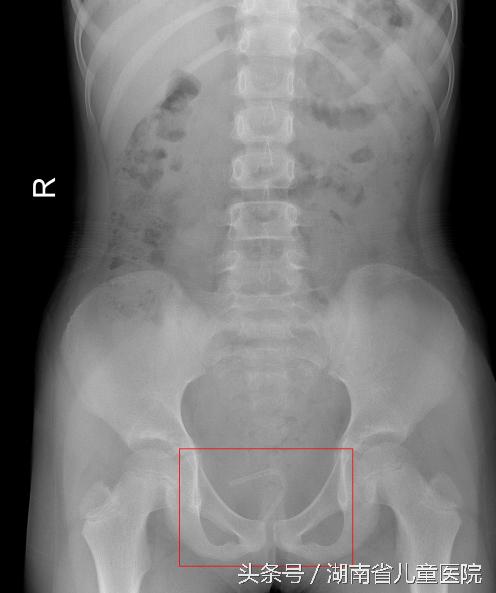

检查发现,阳阳阴道内的异物呈管状,因塞入的过程中用力过猛,管状异物已折叠成 “7”字型。异物一端距阴道口约0.5cm,末端距离阴道口约3cm,同时其右侧端口紧贴孩子的直肠壁和子宫。

询问病史时阳阳妈妈说,孩子平时有时候会搔抓外阴部,但觉得是小孩子好玩就没太在意。 9月1日,医生在输尿管镜下成功从阳阳的阴道内取出了一个直径为10mm的圆形塑料球和一个长约8cm的塑料软管。看到这些东西,阳阳的爸爸妈妈当场震惊了,而这些异物 是什么时候、怎么塞进去的?阳阳却一直支支吾吾,自己也说不清楚。